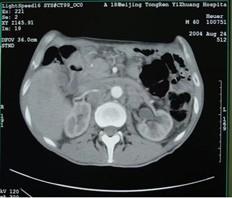

男,60歲,晚期胃癌,腹腔轉(zhuǎn)移,鎖骨上淋巴結(jié)轉(zhuǎn)移,肝,腹腔轉(zhuǎn)移。初治(手術(shù))。治療前CEA 12.95 ng/ml,左鎖骨上轉(zhuǎn)移淋巴結(jié)2.0cm。今又生經(jīng)靜脈滴注,1×1012VP/支/次,3次/周,共30支,聯(lián)合草酸鉑+CF+5-FU化療,2周期。治療后:CEA下降到9.71 ng/ml,左鎖骨上轉(zhuǎn)移淋巴結(jié)縮小到0.5 cm。KPS評(píng)分增加20分,療效評(píng)價(jià)為腫瘤部分消退(PR)。

治療前

治療后